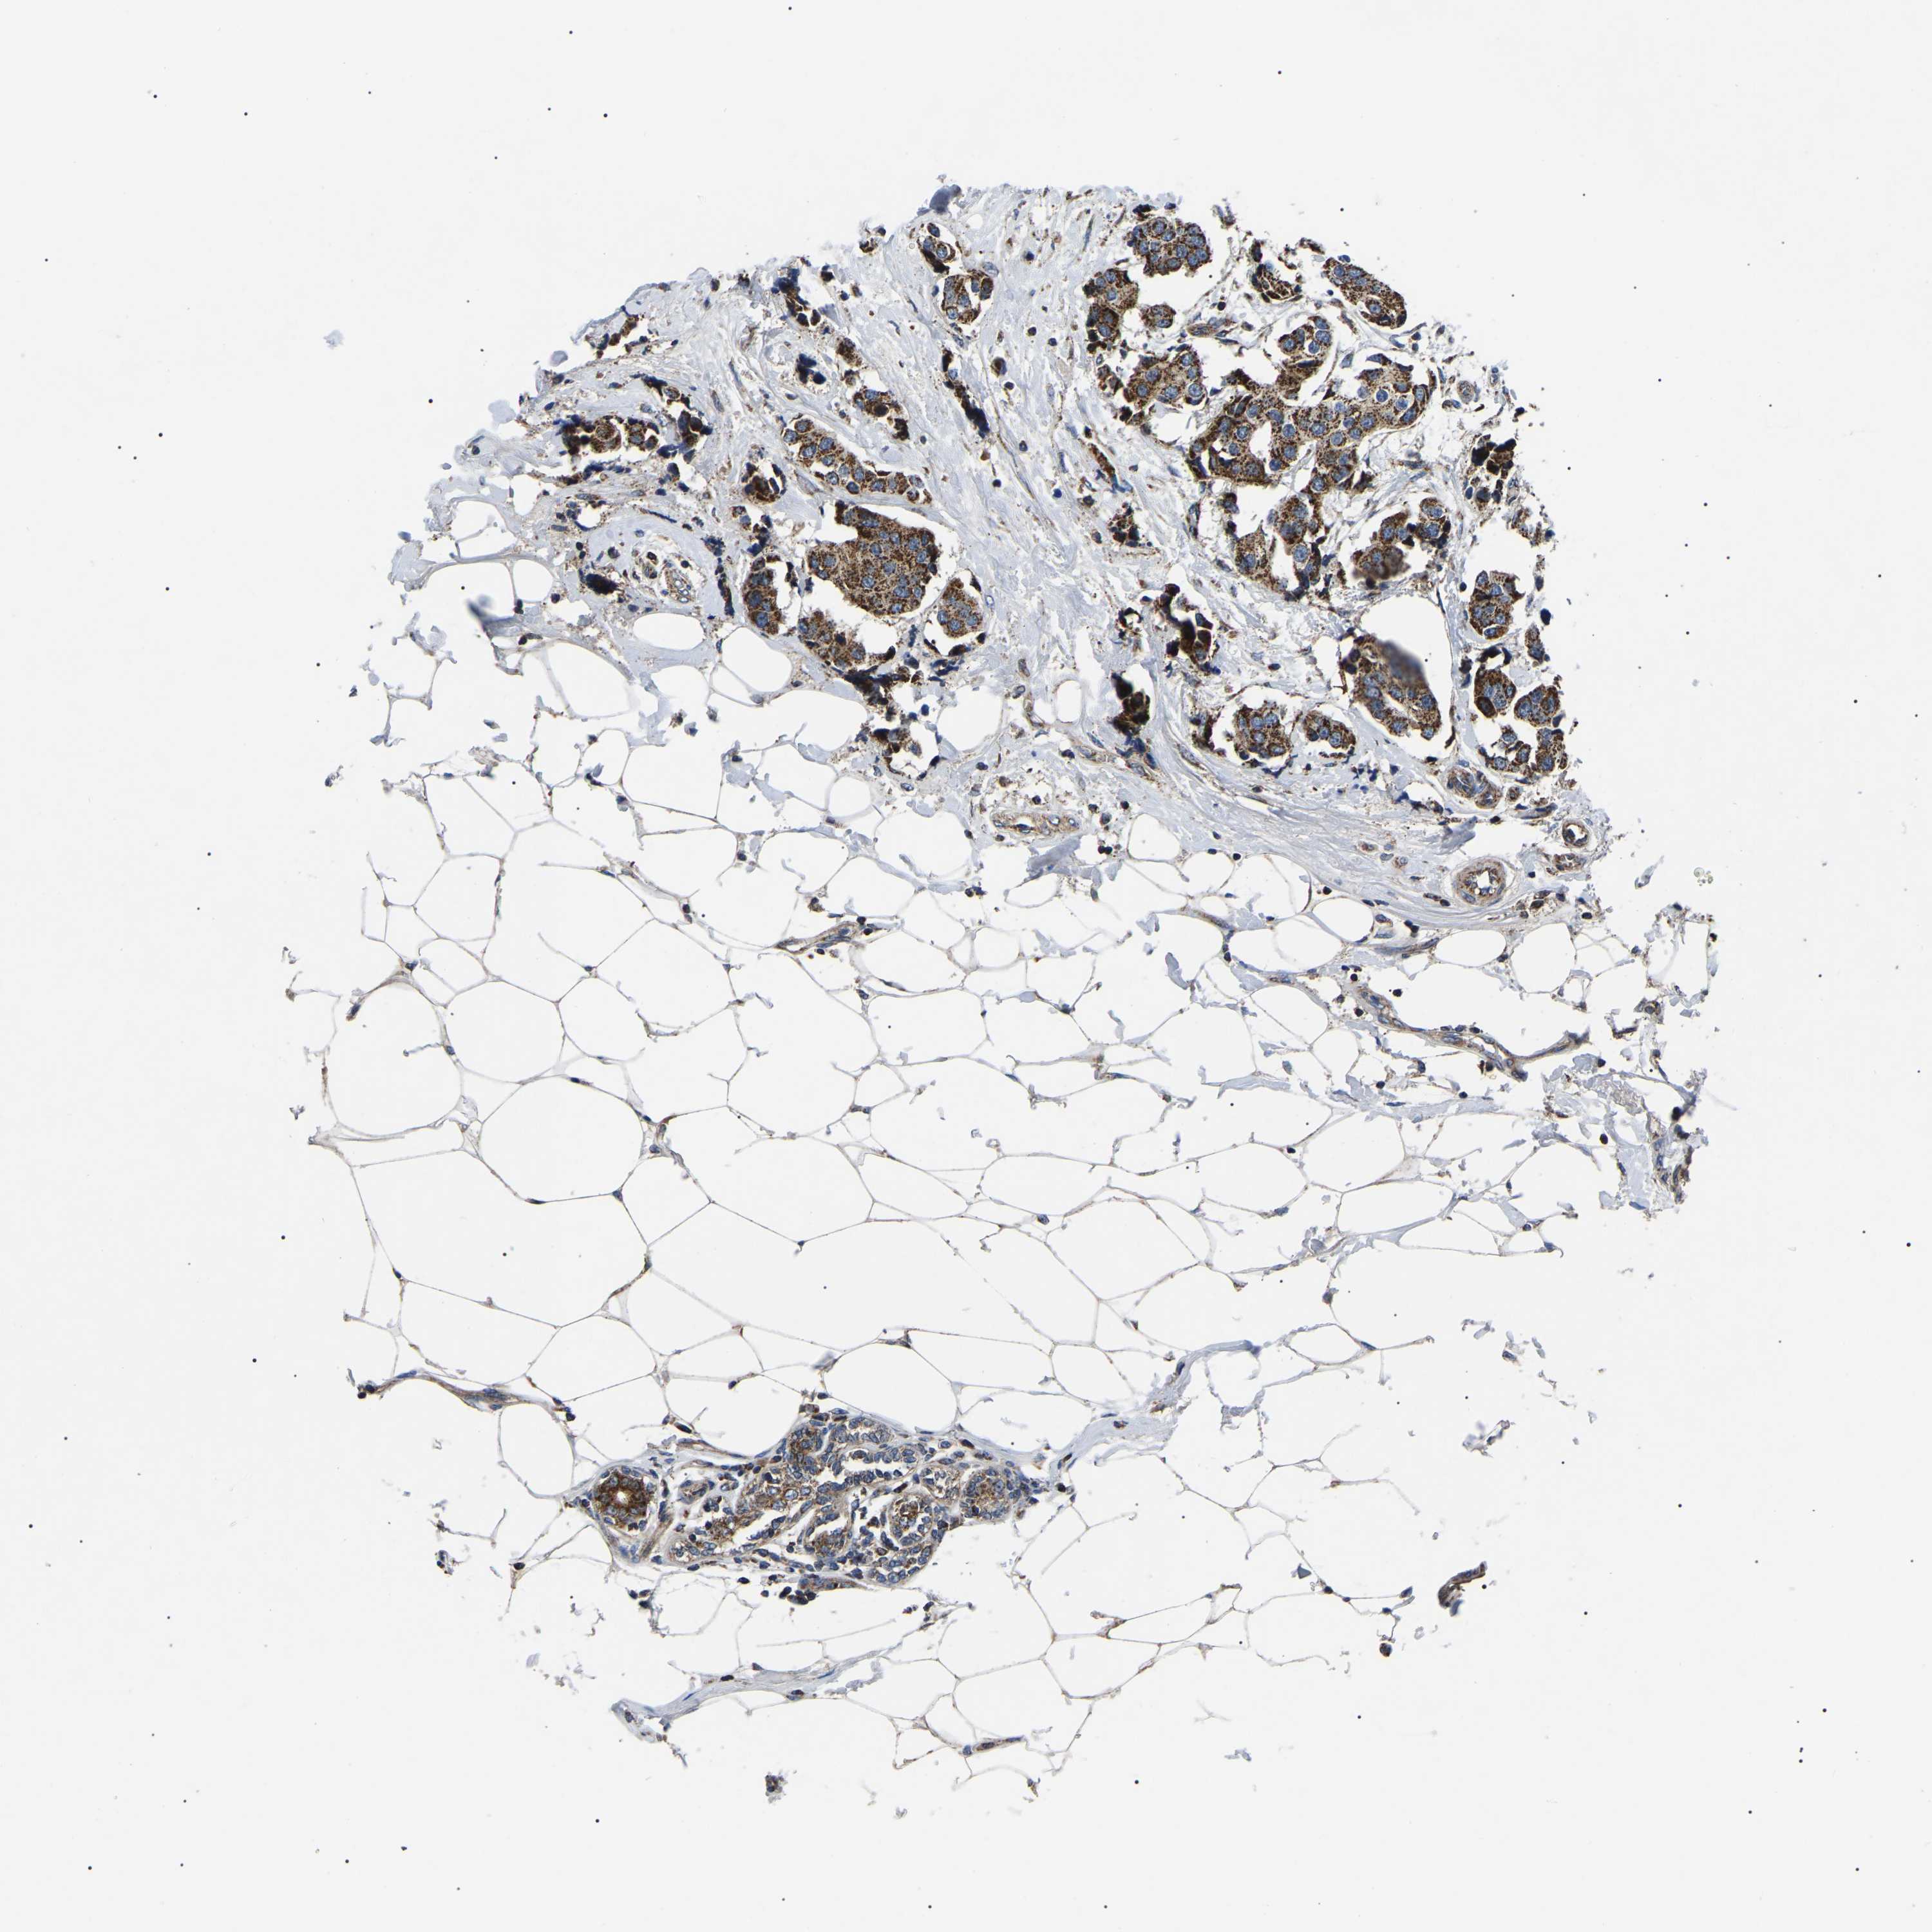

CANCER BREAST CANCER Show tissue menu

BRCA TCGA BRCA VALIDATION PROTEIN EXPRESSION